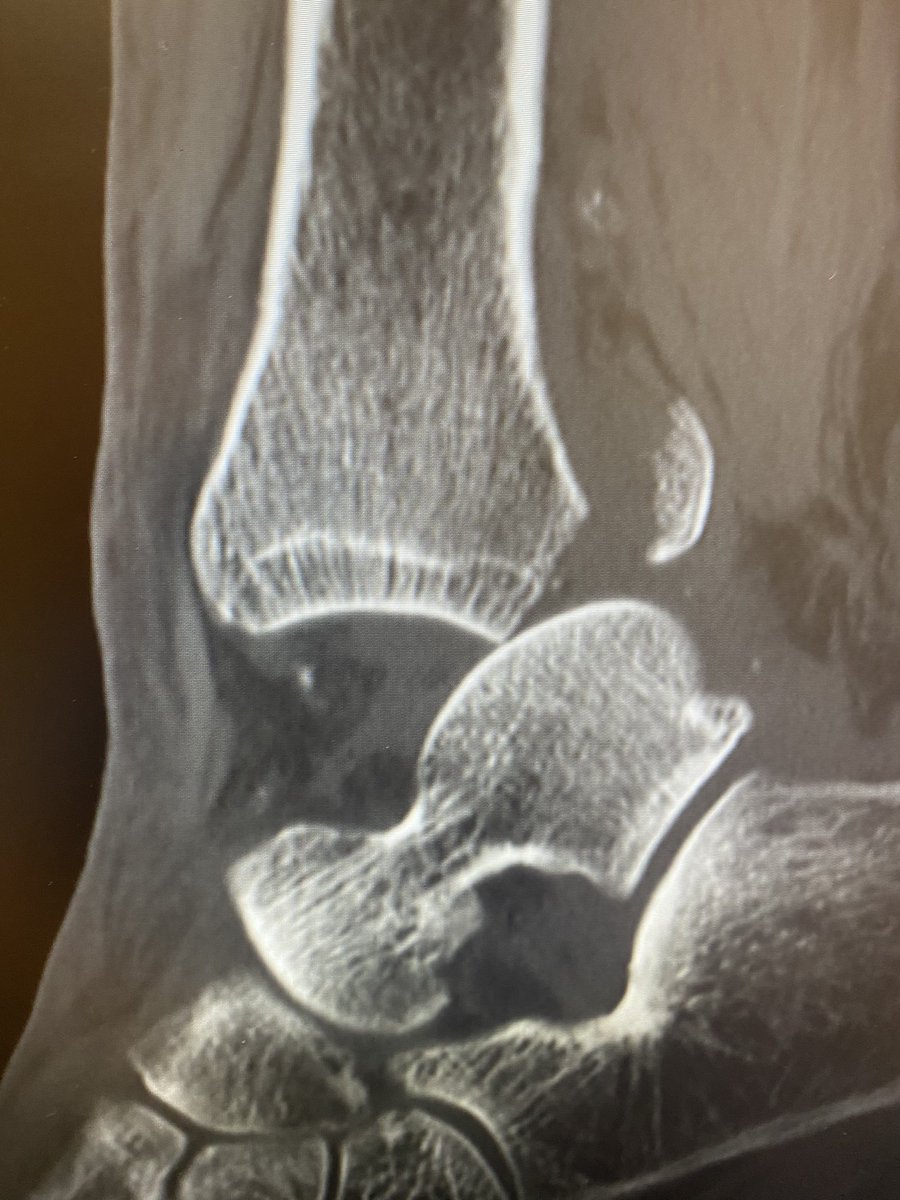

Virginia Beach Orthopedic Foot and Ankle Surgeon